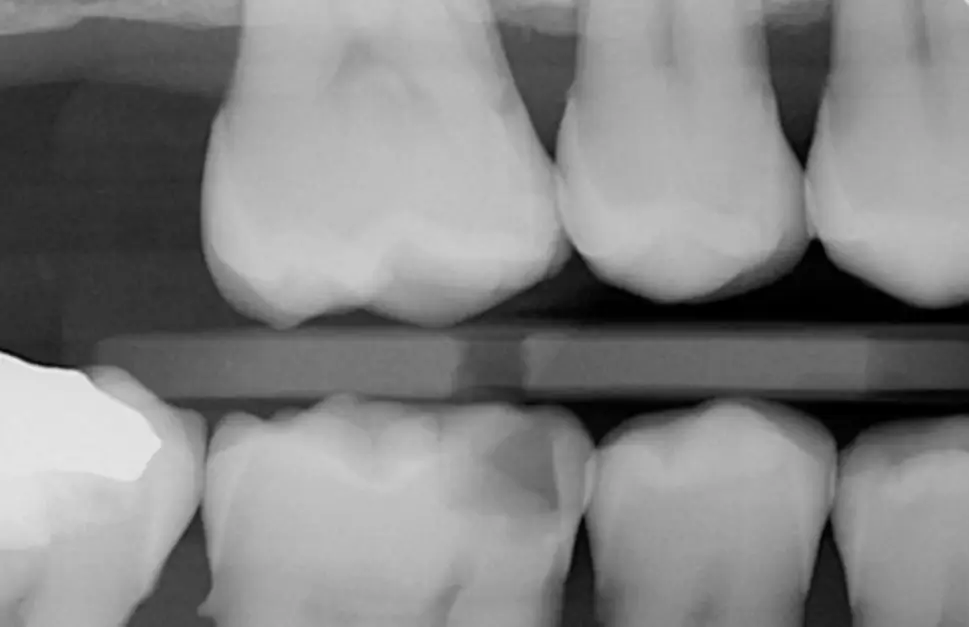

Identify pathology as images are captured

Caries, calculus, periapical radiolucency, and restorations are detected automatically, with no extra steps

AI analyzes each image in the instructor-led student workflows

Visual indicators appear directly in MiPACS at the instructor’s discretion, giving them full control over the curriculum

Help students build confidence in their diagnoses

Consistent, real-time analysis enhances your clinical education process and helps students communicate findings to their patients